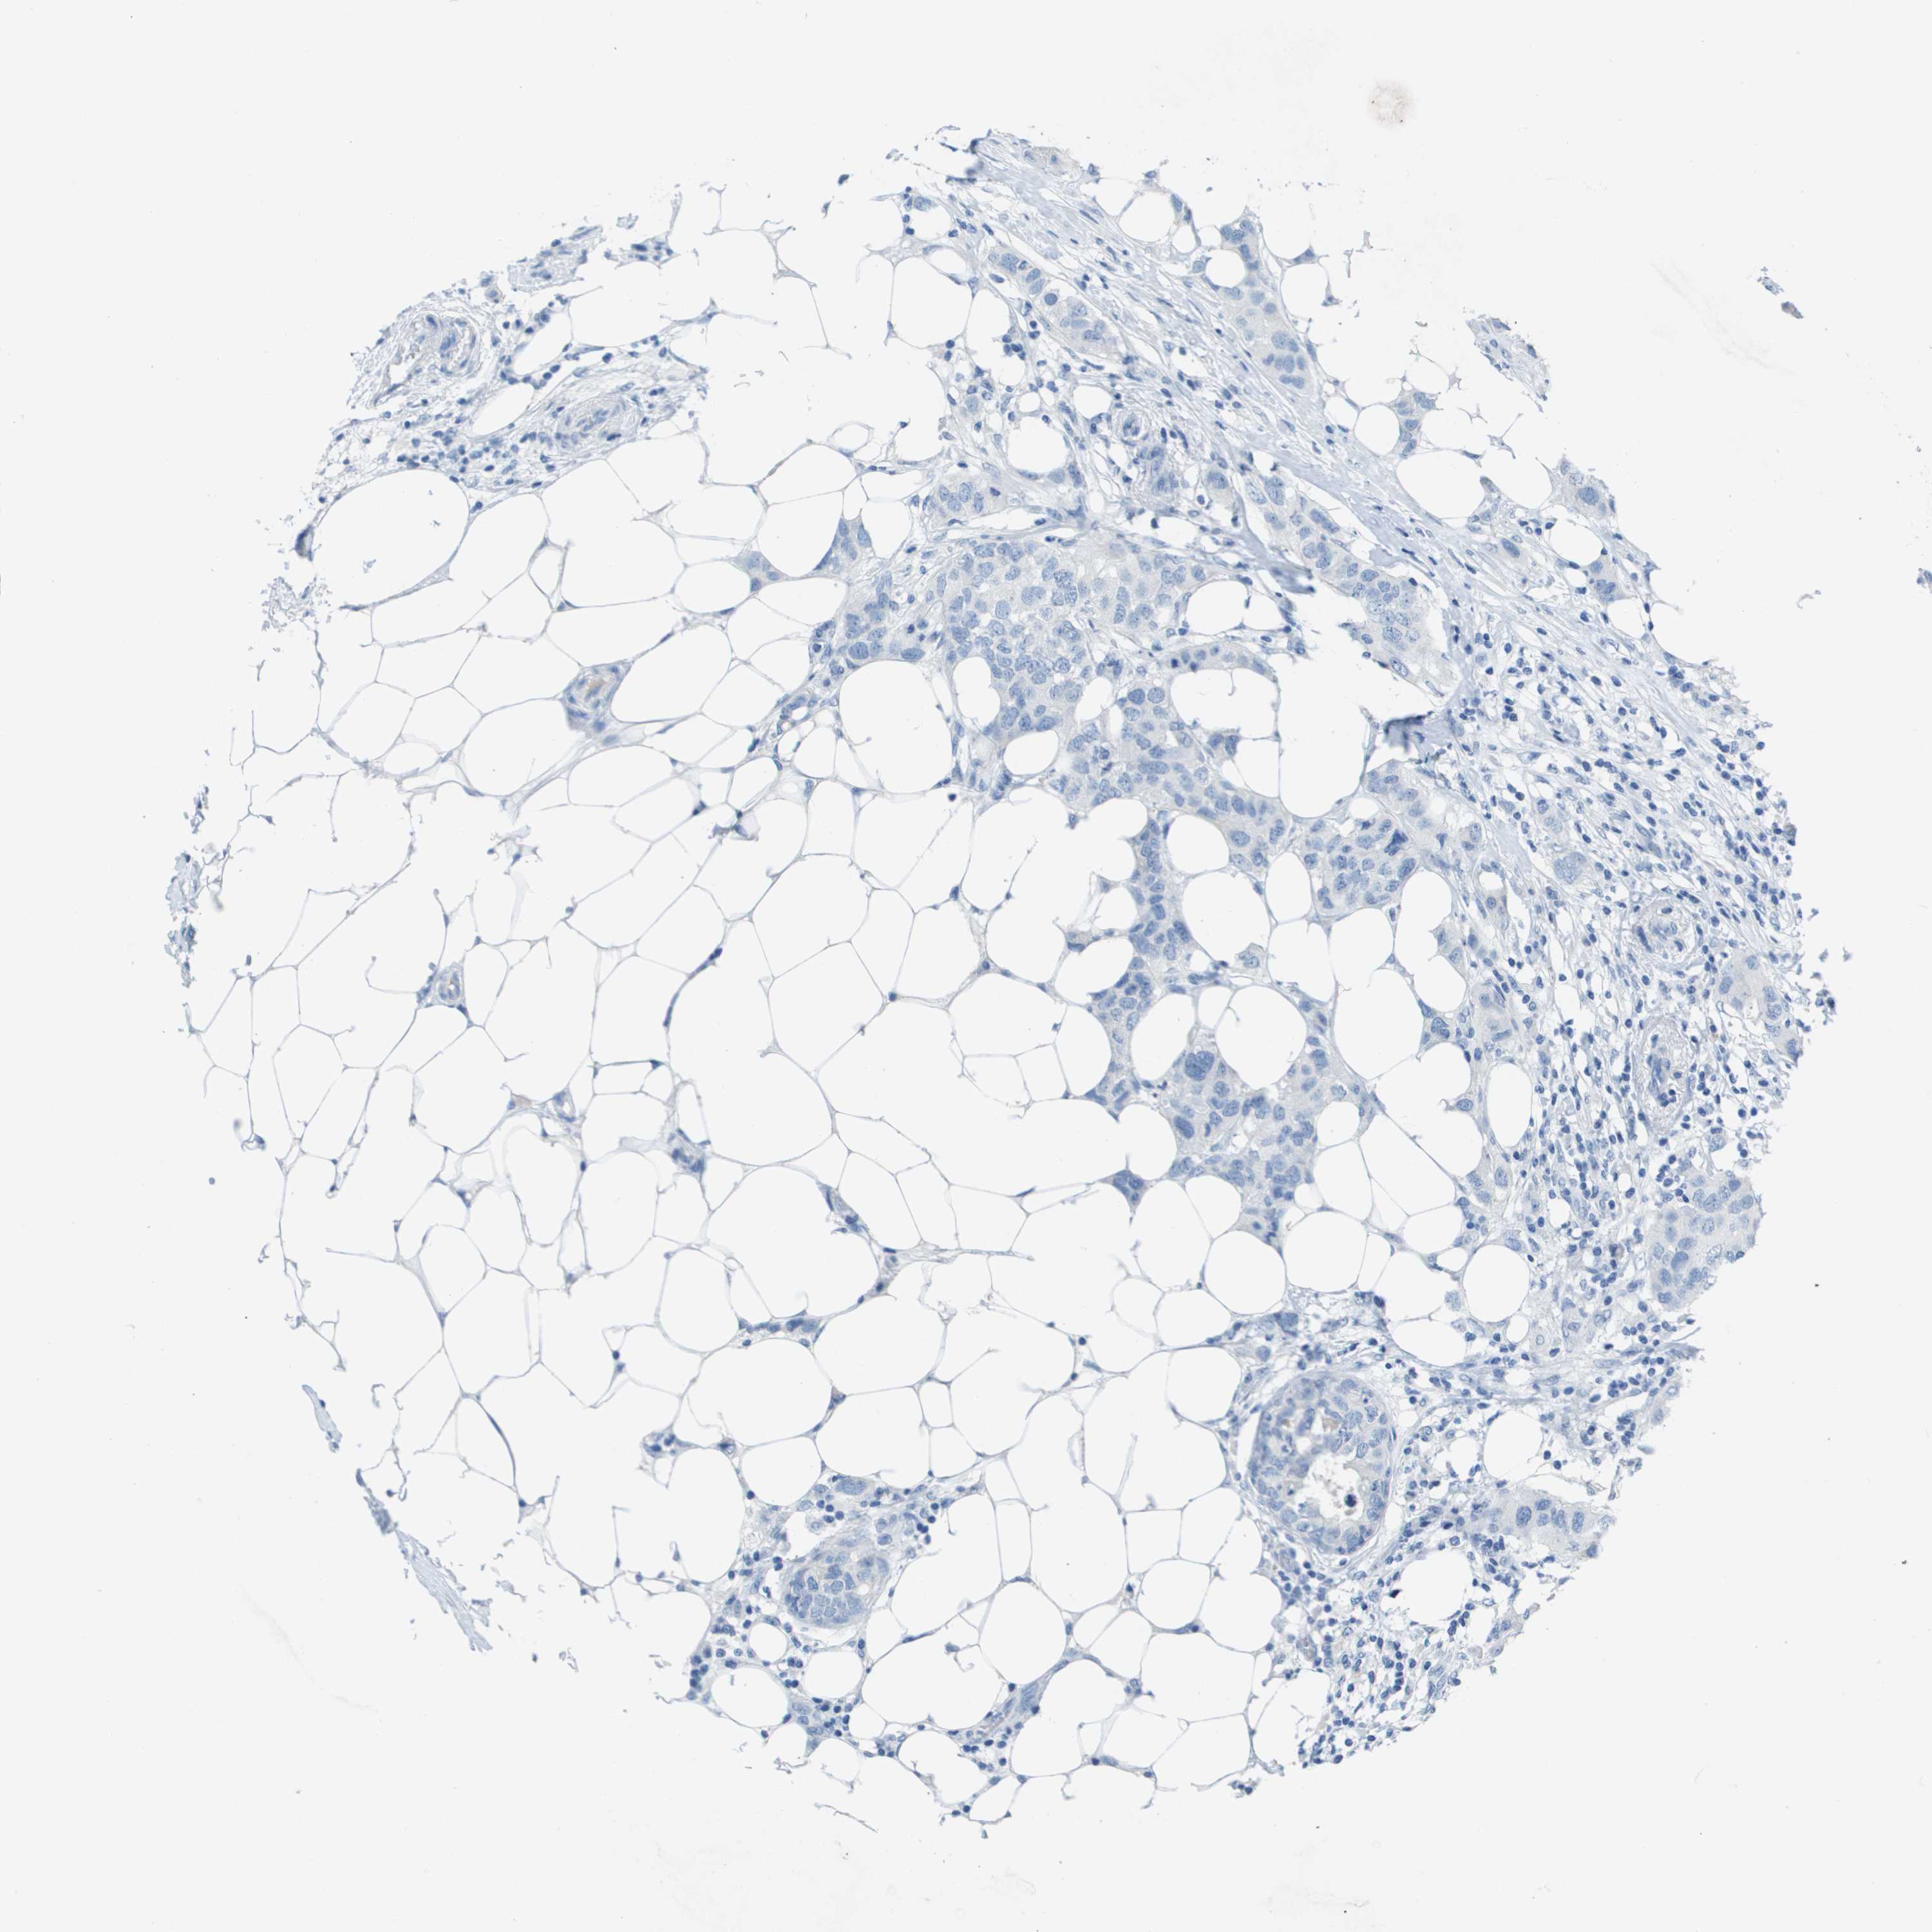

CANCER BREAST CANCER Show tissue menu

BRCA TCGA BRCA VALIDATION PROTEIN EXPRESSION